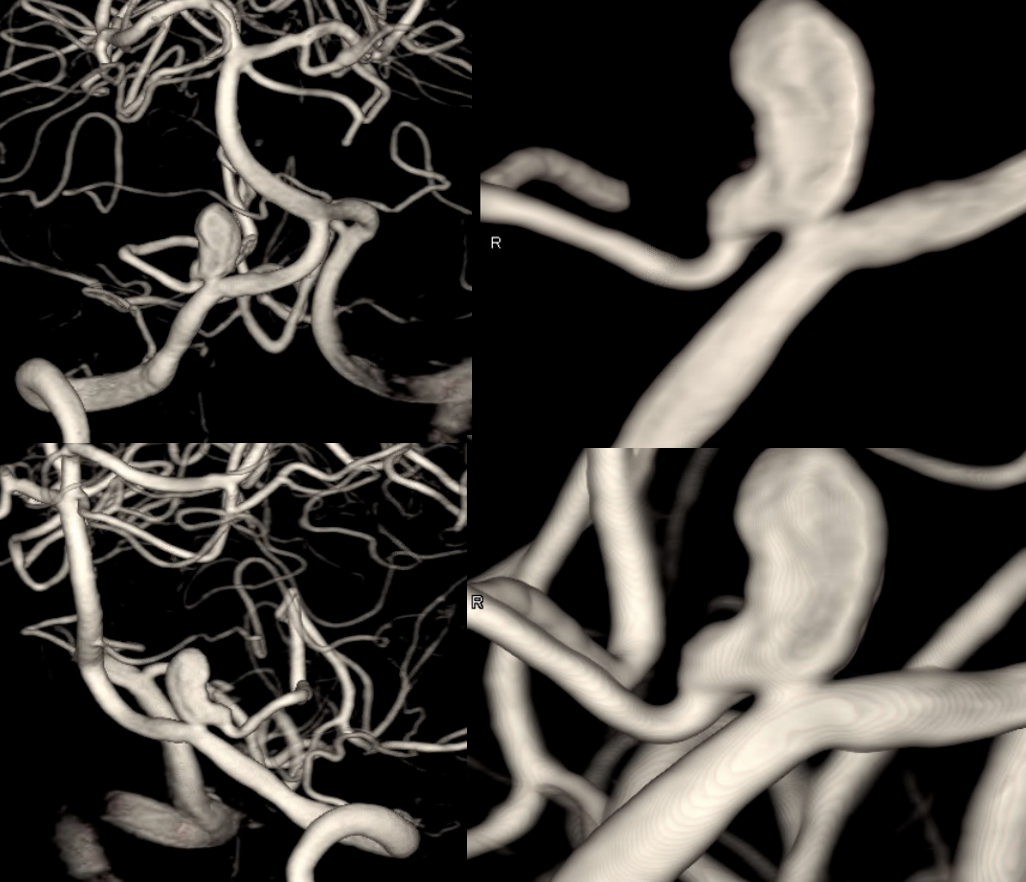

The mistake here would be to hope that some kind of endosaccular treatment will solve the problem. This needs more

PLan to sacrifice right vert and Pipe across VB junction into PICA.

Could one argue that pipe is not necessary. Possibly. The main point is that this needs aggressive solutions before its too late. Flow reversal is key. What if sac is not enough and mass effect worsens? Take that chance or maximize odds of success with a Pipe? We did what we did